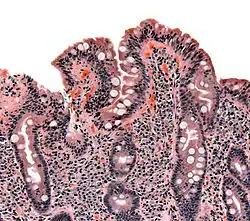

Pathology

The classic pathology changes of coeliac disease in the small bowel are categorised by the "Marsh classification":[111]

- Marsh stage 0: normal mucosa

- Marsh stage 1: increased number of intra-epithelial lymphocytes (IELs), usually exceeding 20 per 100 enterocytes

- Marsh stage 2: a proliferation of the crypts of Lieberkühn

- Marsh stage 3: partial or complete villous atrophy and crypt hyperplasia[112]

- Marsh stage 4: hypoplasia of the small intestine architecture

Marsh's classification, introduced in 1992, was subsequently modified in 1999 to six stages, where the previous stage 3 was split in three substages.[113] Further studies demonstrated that this system was not always reliable and that the changes observed in coeliac disease could be described in one of three stages:[22][114]

- A representing lymphocytic infiltration with normal villous appearance;

- B1 describing partial villous atrophy; and

- B2 describing complete villous atrophy.

In untreated coeliac disease, villous atrophy is more common in children younger than three years, but in older children and adults, it is common to find minor intestinal lesions (duodenal lymphocytosis) with normal intestinal villi.[11][29]